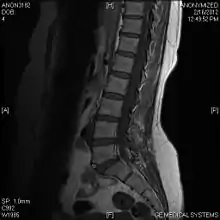

A limbus vertebra is a bone tubercle formed by bone trauma on a vertebral body, bearing a radiographic similarity to a vertebral fracture. The anterior-superior corner of a single vertebra is the common site for this defect although it can also be seen at the inferior corner as well as the posterior or anterior margin. Anatomically, it is assumed to be an intra-vertebral body herniation of the disc material occurring during adolescent growth spurt when the ring apophysis has not yet fused. It was first described by Schmorl in 1927[1] and later in detail by Leif Sward and Adad Baranto.

Viewed in a lateral radiograph, it appears as a triangular shaped bone fragment, not unlike an anterior lip fracture, but with softer edges.

Limbus vertebra is not always symptomatic, but severe cases may lead to more serious pathological conditions and chronic pain. In rare instances, a posterior limbus vertebra has been described causing radiculopathy due to nerve root compression. [2]